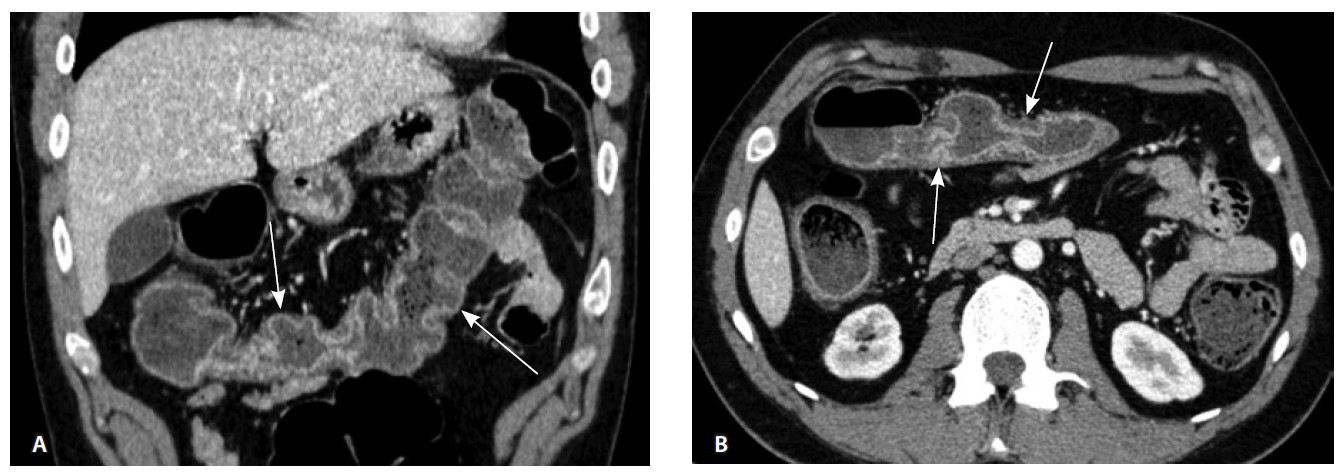

При мультиспиральной компьютерной томографии органов брюшной полости визуализировалась картина диффузного утолщения стенки толстой кишки с умеренным утолщением брыжейки и минимально выраженными явлениями лимфаденопатии в брыжейке (рис. 1).

Рис. 1. Мультиспиральная компьютерная томография органов брюшной полости с внутривенным введением контрастного вещества (йомепрол 350–100 мл), артериальная фаза: А – фронтальная проекция, Б – аксиальная проекция. Стрелками указано диффузное утолщение стенки толстой кишки и брыжейки